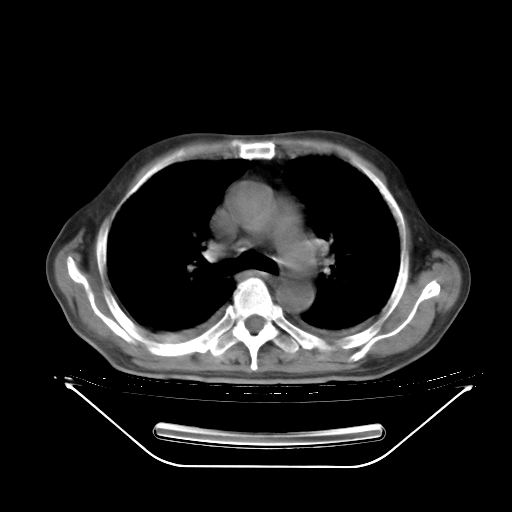

今天复查肺部CT,发现双肺广泛磨玻璃样改变。所以我把3月19日和5月9日相隔50天的肺部CT上传。请大家会诊。

2009年3月19日肺部CT片。

5月9日肺部CT(在4月27日齐鲁医院肺部CT描述部分肺组织磨玻璃样改变,12天后肺组织广泛磨玻璃样改变)

大致读了系列胸部CT:纵隔窗无明显异常,肺窗:从4、27至今:主要是双肺中下野外带可见毛玻璃样改变,目前处于急性肺泡炎阶段,至于原因考虑1、结替组织或胶原血管性疾病所致?2、恶性疾病如恶组在肺部所致的表现或细支气管肺泡癌?3、药物或其它原因如肺蛋白沉着症所致肺泡炎目前不太可能?总之,明天就去请我院的呼吸科、感染科、血液科和临免专家会诊哈。